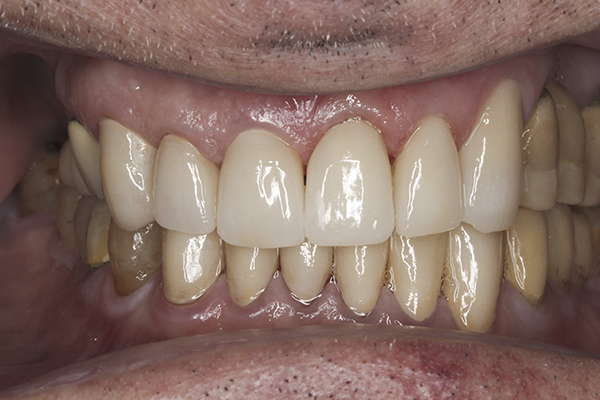

(35.) Postoperative right lateral, closed view.

Figure 35

(36.) Postoperative anterior, closed view. Note the position of the upper and lower canines to provide canine guidance.

Figure 36

(37.) Postoperative left lateral, closed view.

Based on examination of the mounted models, it was decided to treat the patient in centric relation and an additive equilibration approach was used to idealize the planes of occlusion. On the articulator, the patient’s first point of contact in centric relation was the starting point and an additive equilibration technique was implemented, building the teeth to meet ideally at the patient’s first point of contact. A diagnostic wax-up was completed on the mounted models to determine where the anterior and posterior teeth needed to be in space. A template from the wax-up was used to fabricate the anterior provisional restorations. The anterior teeth were restored with full-coverage restorations, creating ideal stops between the lower incisal edges and upper cingulums. The maxillary incisal edges were placed to provide proper phonetics and an acceptable esthetic outcome, while still working within the envelope of function. All of these parameters are worked out in the provisionals prior to moving forward with definitive restorations. With the anterior provisionals in place, posterior composite tops were bonded to his existing dentition, creating ideal centric stops on the posterior teeth. The anterior and canine guidance was developed, resulting in immediate separation of the posterior teeth during all excursive movements (Figure 17 through Figure 28). Once the author and patient were happy with the function, esthetics, phonetics, and comfort of the provisionals, an impression of the approved provisionals was taken and sent to the laboratory to use as a guide in the fabrication of the final anterior crowns. With the final restorations delivered, the patient was extremely happy with his new smile. Most importantly, proper anterior and canine guidance in harmony with his envelope of function was achieved, which resulted in comfortable function and immediate separation of the posterior teeth during protrusive and lateral excursions (Figure 29 through Figure 42).